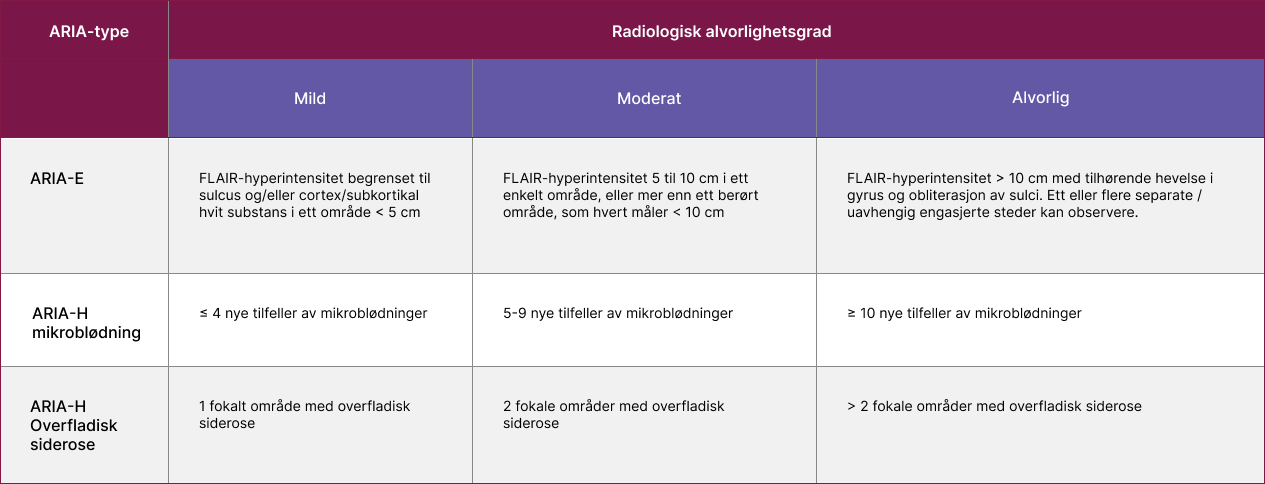

Radiologisk alvorlighetsgrad

Kriterier for MR-klassifisering av ARIA

| ARIA-E | FLAIR-hyperintensitet begrenset til sulcus og/eller cortex/subkortikal hvit substans i ett område < 5 cm | FLAIR-hyperintensitet 5 til 10 cm i ett enkelt område, eller mer enn ett berørt område, som hvert måler < 10 cm | FLAIR-hyperintensitet > 10 cm med tilhørende hevelse i gyrus og obliterasjon av sulci. Ett eller flere separate / uavhengig engasjerte steder kan observere. |

| ARIA-H mikroblødning | ≤ 4 nye tilfeller av mikroblødninger | 5-9 nye tilfeller av mikroblødninger | ≥ 10 nye tilfeller av mikroblødninger |

| ARIA-H Overfladisk siderose | 1 fokalt område med overfladisk siderose | 2 fokale områder med overfladisk siderose | > 2 fokale områder med overfladisk siderose |